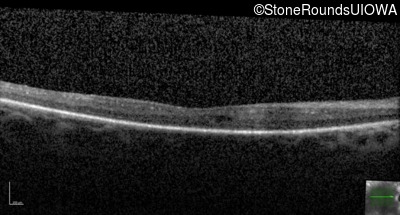

Optical Coherence Tomography - Left - 20/80 +2

Exemplar / OCT Stack